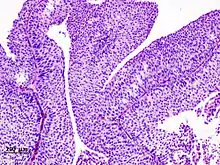

The 1973 WHO grading system for transitional cell carcinomas (papilloma, G1, G2 or G3) is most commonly used despite being superseded by the 2004 WHO[14] grading for papillary types (papillary neoplasm of low malignant potential [PNLMP], low grade, and high grade papillary carcinoma). High-grade carcinoma typically displays more pleomorphism, multiple mitoses, euchromatin and relatively prominent nucleoli, and uneven distribution of nuclei.

Histopathology of urothelial carcinoma of the urinary bladder.